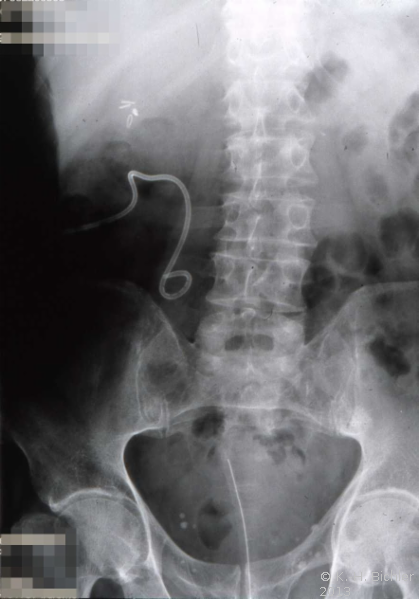

Als Komplikation ausgedehnter Mündungsdivertikel kommt es zu Abflussbehinderungen mit entsprechender Beeinträchtigung der Nierenfunktion. Als Beispiel die Harnstauungsniere bei einem Erwachsenen mit Abflussbehinderung durch ein ausgedehntes Mündungsdivertikel. Zunächst Harnableitung, dann Divertikelabtragung und Reimplantation (Abbildung HG1).